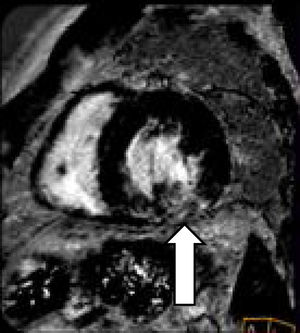

El paciente siguió tratamiento vasodilatador, y en el control clínico a los 2 meses se encontraba normotenso y asintomático. Un nuevo ecocardiograma transtorácico no mostró cambios respecto del anterior, excepto una mejoría de la función sistólica. El ecocardiograma transesofágico confirma los datos descartando foramen oval permeable. Se repite CRM que muestra: ventrículo izquierdo con hipertrofia concéntrica moderada, no dilatado, sin alteraciones de la contractilidad segmentaria y función sistólica normal (FE 70%) y persistencia del patrón parcheado intramiocárdico en el segmento medio inferolateral e inferior del ventrículo izquierdo sin necrosis, sugerente de sarcoidosis versus enfermedad de Fabry.

Hallazgos morfológicos e inmunofenotípicos compatibles con lesión fibroinflamatoria mediastínica relacionada con IgG4. La IgG4 sérica es de 130mg/dl. Las baciloscopias y cultivos para micobacterias de las muestras obtenidas fueron negativas, y se descartó por completo la presencia de proceso linfoproliferativo. Con el diagnóstico de enfermedad relacionada con IgG4 con afectación mediastínica y, probablemente, cardíaca, se inicia tratamiento inmunosupresor con prednisona (1mg/kg/día) y azatioprina (a dosis crecientes hasta 2mg/kg/día). El paciente presenta buena respuesta clínica, con reducción de las imágenes de adenopatías detectadas por TC, así como la CRM de control que, tras 4 meses de tratamiento inmunosupresor, muestra reducción del patrón intramiocárdico descrito anteriormente en el segmento medio inferolateral e inferior del ventrículo izquierdo sin necrosis (fig. 2).